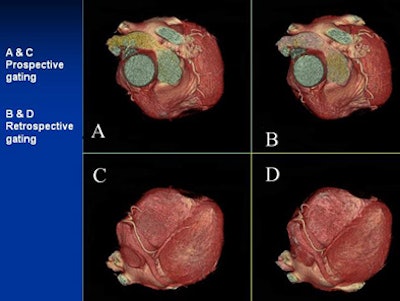

| Can you tell the difference between the low-dose prospectively gated and and higher-dose retrospectively gated coronary CTA images above and below? The acquisition method for each image is marked. |

![]() |